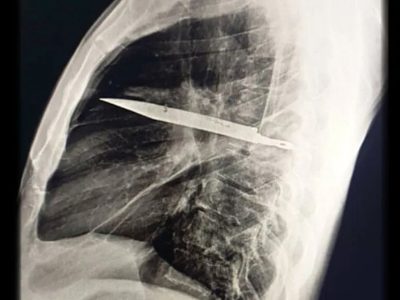

• چاقویی که هشت سال در «سینه» مخفی مانده بود

چاقویی که هشت سال در «سینه» مخفی مانده بود

مردی تانزانیایی متوجه عفونت در سینه خود شد و پس از بررسی‌های پزشکی، مشخص شد تیغه چاقویی در حفره قفسه سینه او باقی مانده است.